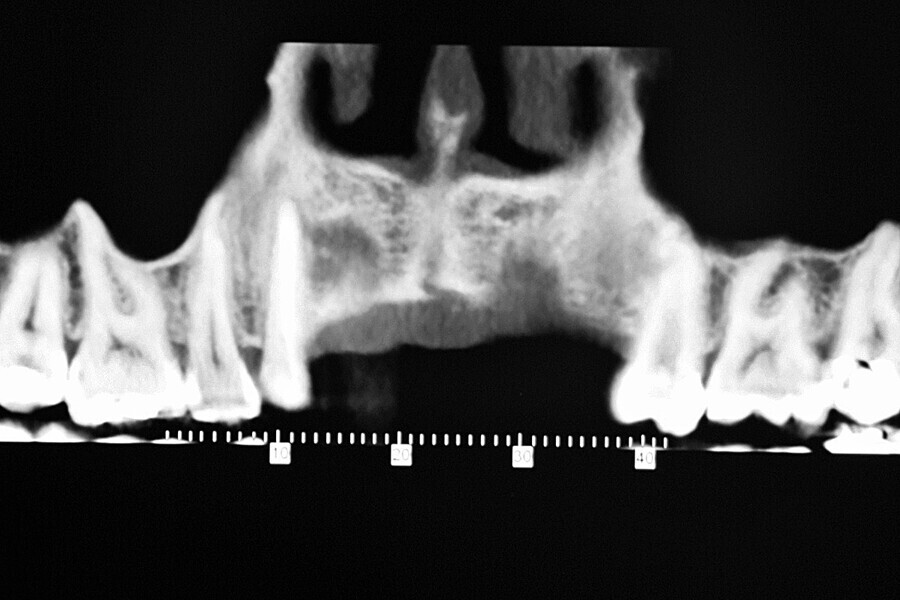

Fig. 40: Radiographic check-up after seven years.